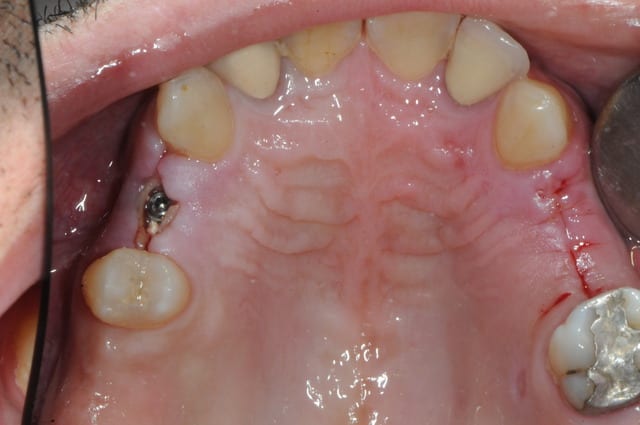

dis moi la tu le trouves comment mon compromis avec l'espace biologique

eii

d'après toi faites il y a combien de temps?

Superbe ratrapage suite à une operculisation d'une vis de couverture. Félicitations. Je te savais costaud béotien mais là tu m'impressionnes vraiment.

- pas de vis de couverture , pas d'operculisation!!

Même pas de lambeau pédiculé palatin!

Wouaww les photos beotien !! Quel progrès ! Super !

Oui c'est bon l'humour en fin de semaine. Content que tu le comprennes.

Félicitations sincères, beau résultat.

Surtout n'arrête pas de mettre des photos!